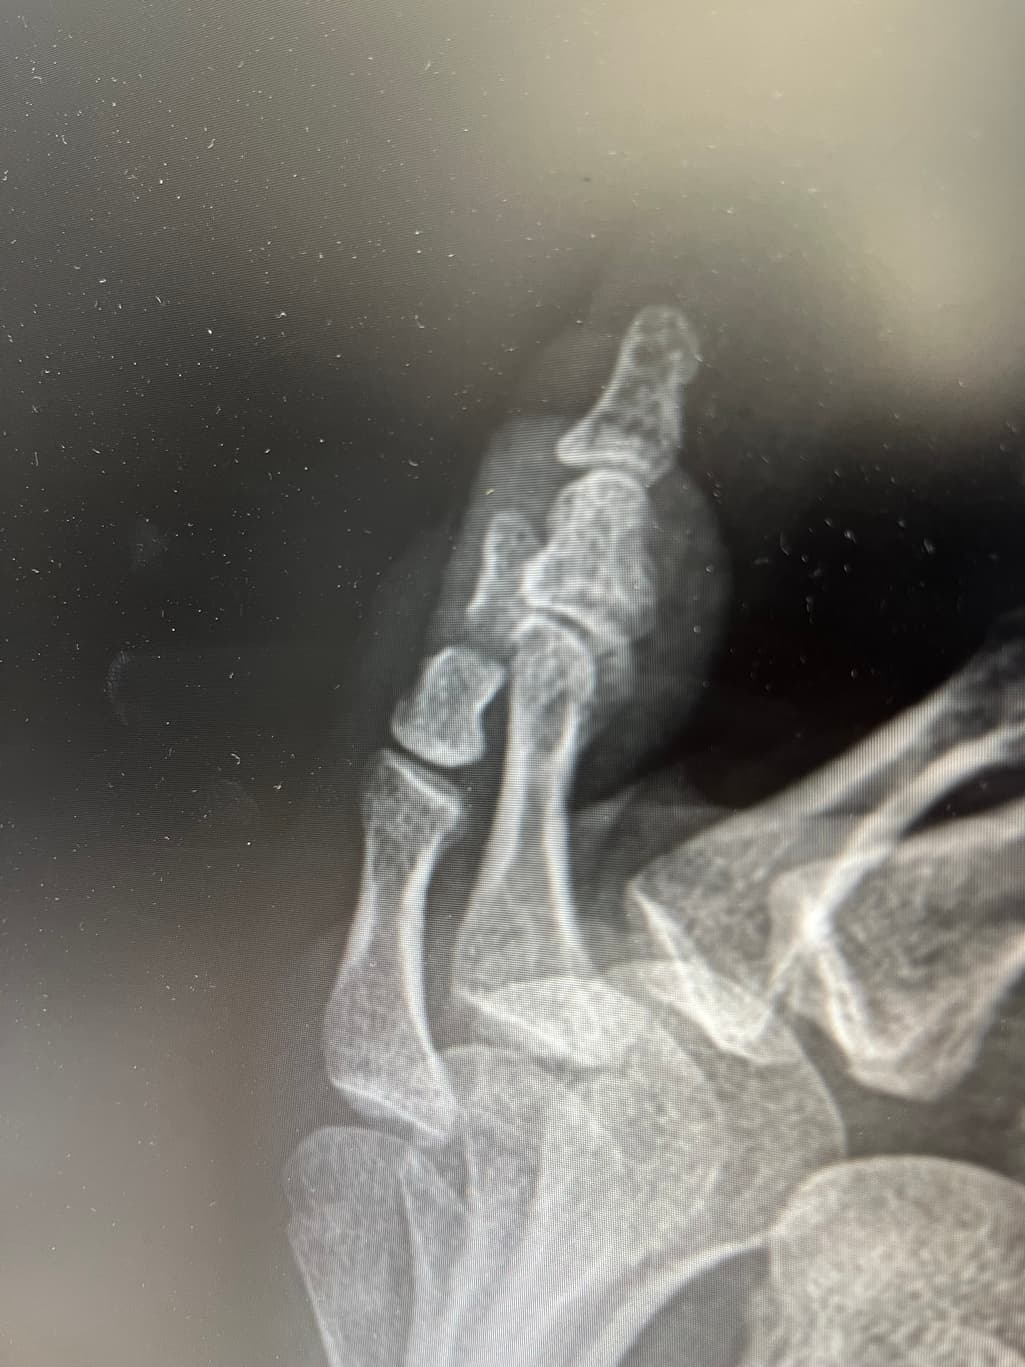

새끼발가락 골절, 수술 필요할까요?

현재 테이핑+ 반깁스 중입니다

수술 추천하시는데 고민이 되어서요

비수술치료는 어려울까요?

새끼발가락 골절의 경우 비수술적 치료가 가능한 경우가 많습니다. 테이핑과 반깁스는 일반적으로 초기 치료에 효과적일 수 있어 골절이 단순하고 이동이 적은 경우 수술 없이도 회복이 가능합니다. 그러나 골절의 위치와 변위 정도에 따라 수술이 필요할 수 있으므로 정확한 진단을 바탕으로 의사와 상의해 결정하는 것이 중요합니다!